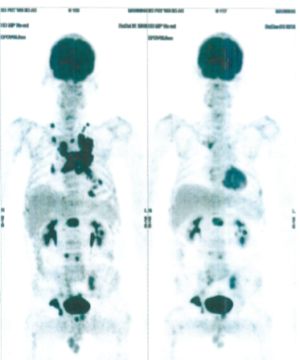

CASE NO: 5 (BREAST CANCER)

A middle-aged woman with breast cancer that has spread to the anterior chest wall, and numerous chemotherapy could not stop the spread of cancer. After a few treatment, almost all the cancer went into remission. About 6 months later, she is still in remission.

CASE NO: 6 (BREAST CANCER)

A middle-aged women treated for breast cancer now presents with massive liver metastases and a few bone metastases. She refused conventional chemotherapy and came to see us. After just 2 treatment, most of the cancer went into remission and those remaining are less active. Treatment will continue until complete remission.

CASE NO: 7 (BREAST CANCER)

A middle-aged woman treated for breast cancer now presents with bone and liver metastases. After a few treatment, most of the cancer went into remission, and the remaining ones are less active.

CASE NO: 8 (BREAST CANCER)

A middle-aged women treated for breast cancer now present with bone and right lung metastases. After just 2 treatment, almost all the cancer went into remission, but treatment is continuing to prevent recurrence.